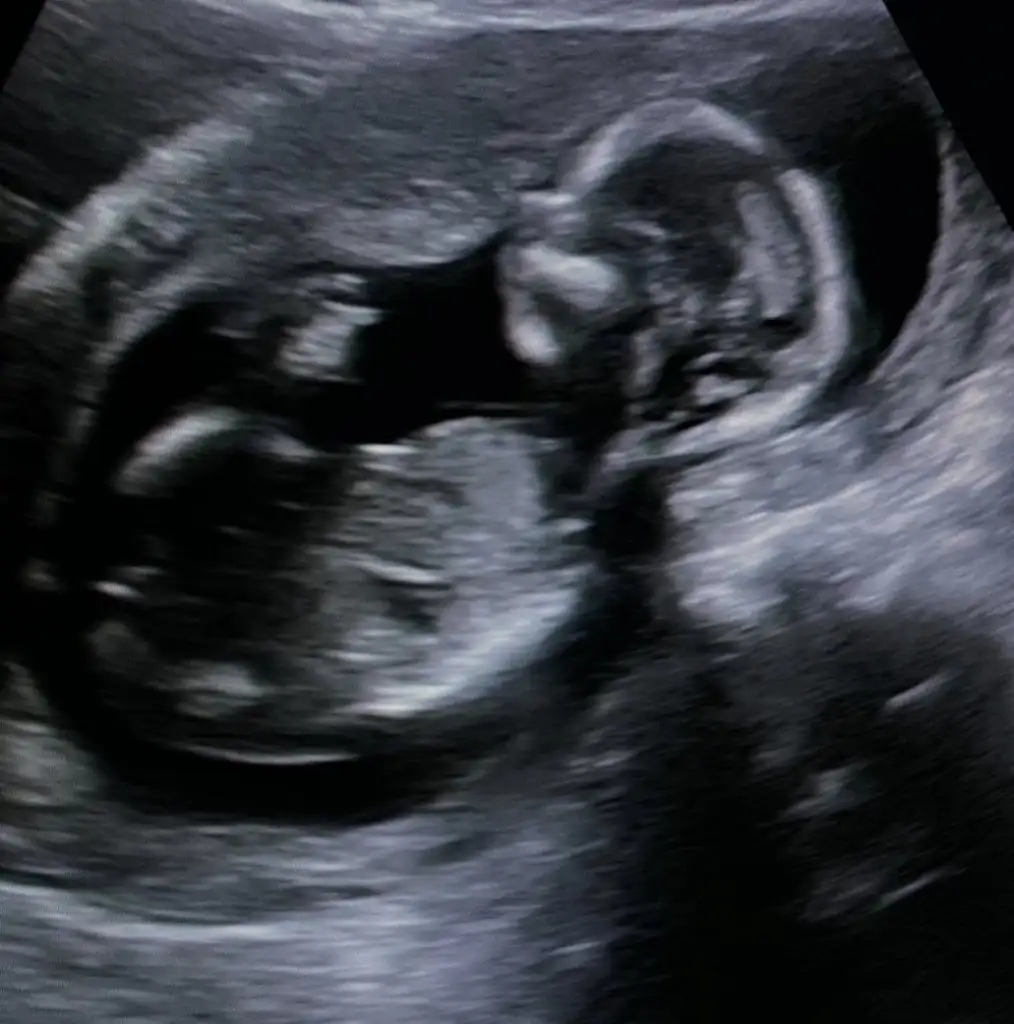

5 ve 14. haftaya kadar olan ultrason fotolarınızı paylaşın. Vajinadan mı yoksa karından mı çekildiğini ve kaç haftalık olduğunu da mutlaka belirtin.

Benimlinede bakabilir misinizyolk sac nasıl değiştirmiş yerinibebeğiniz solda görünüyor erkek gibi

Prenses gibiBenimlinede bakabilir misiniz

Erkek görünüyorMerhaba bana da tahminde bulunabilir misinizkarından usgEki Görüntüle 3073103